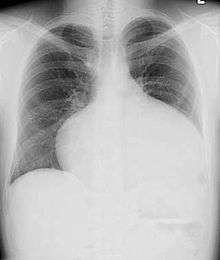

Adults with an uncorrected ASD present with symptoms of dyspnea on exertion (shortness of breath with minimal exercise), congestive heart failure, or cerebrovascular accident (stroke). They may be noted on routine testing to have an abnormal chest X-ray or an abnormal ECG and may have atrial fibrillation. If the ASD causes a left-to-right shunt, the pulmonary vasculature in both lungs may appear dilated on chest X-ray, due to the increase in pulmonary blood flow.[40]